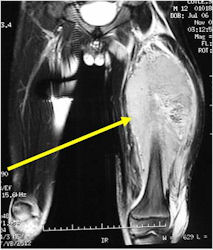

- Soft Tissue Mass in 90% of of cases

- Most protocols administer preoperative chemotherapy then surgery is performed. Surgery is followed by several courses of postoperative chemotherapy.

- Ewing sarcoma responds well to chemotherapy. Often there is a dramatic reduction in size of the tumor.

- Most common chemotherapy agents utilized include as of 2008: Vincristine, Adriamycin, Cyclophosphamide, Actinomycin-D, Ifosfamide, Etoposide

- Lesions grossly confined to bone have a better prognosis than those with a soft tissue component

- Response to preoperative chemotherapy: Greater than 90% tumor necrosis (Good response) correlates with a better prognosis

- Tumors greater than 8cm in maximum dimension and those with greater than a volume of 100cc have been associated with a worse prognosis